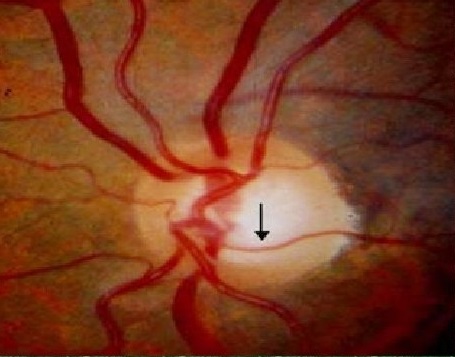

이후 시간이 지나면서, 녹내장이 더 진행되어, 창백한 부위에 함몰이 발생하게되면,

함몰에 따라서 혈관이 실제로 움푹패이면서, 혈관이 공중에 뜬 상태가 됩니다.

이러한 상태를 Baring of the circumlinear vessel, 약어로 BCV 라고 합니다.

이는 함몰로 인해서 시신경유두위의 혈관의 모양이 Baring 드러난다는 것을 의미하는 것으로,

혈관이 공중에 뜬상태로 함몰된 부위 위쪽을 지나가는 상태를 말합니다.

이후에는 결국 혈관 역시 압력을 받아 그 아래의 유두함몰부위로 움푹들어가면서 혈관주행의 변화를 보이게됩니다.